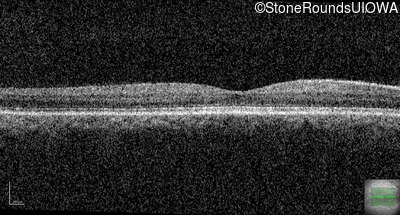

Optical Coherence Tomography - Left - 20/160 -1

Exemplar / OCT Stack